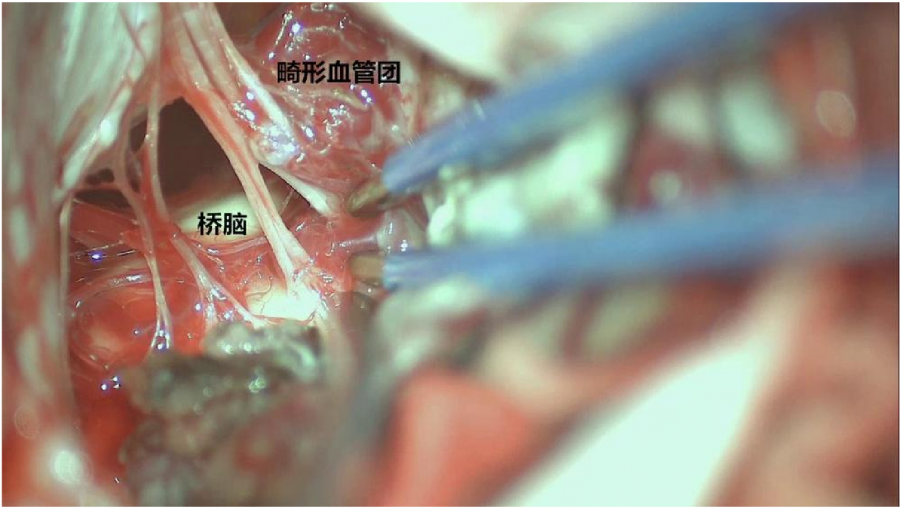

⾏左侧远外侧⼊路脑⼲⾎管畸形切除术,术中所⻅: